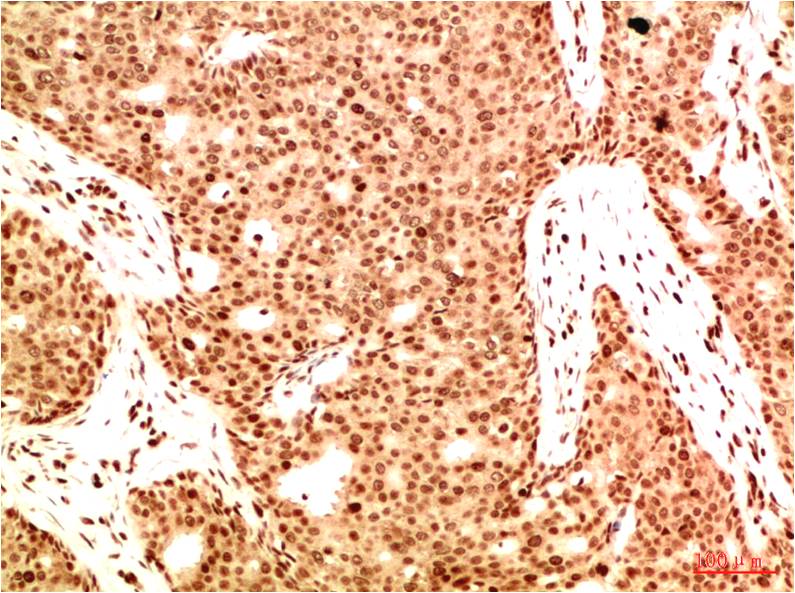

Product name: Acetyl NF kB P65(K314/K315) (5G11) Mouse mAb

Dilutions: IHC 1:100-200

Cellular localization: Cytoplasm,?Nucleus